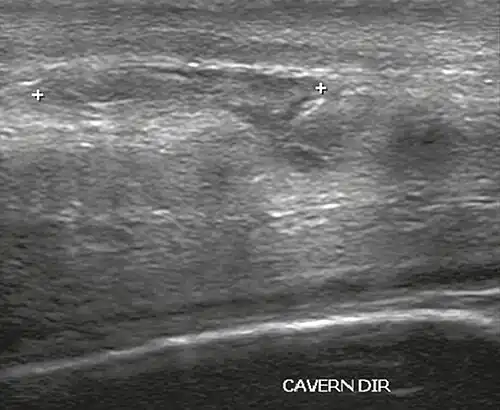

In the ultrasound examination, a lesion of the tunica albuginea presents as an interruption in (loss of continuity of) the echoic line representing it (Figure 4). Small, moderate, or broad hematomas demonstrate the extent of that discontinuity. Intracavernous hematomas, sometimes without the presence of a tunica albuginea fracture, can be observed when there is a lesion of the smooth muscle of the trabeculae surrounding the sinusoid spaces or the subtunical venular plexus.[2]

Figure 4 A: Ultrasound of the penis, right lateral view. Longitudinal section showing rupture of the tunica albuginea with an adjacent 1.92 cm hematoma (between calipers), due to trauma.[2] -